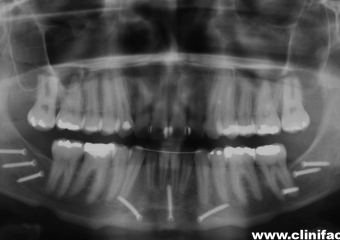

Raio x panorâmico inicial